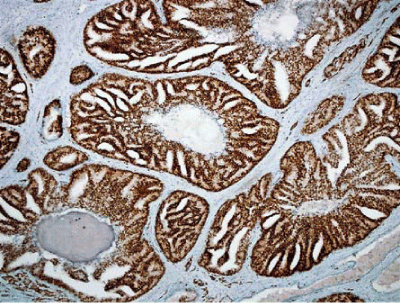

Pathobiological Study of Leiomyomatoid Angiomatous Neuroendocrine Tumor (LANT)- Like Tumor in the Myometrium

Takuma Hayashi1*, Tomoyuki Ichimura2, Kenji Sano3, Dorit Zharhary4, Hiroyuki Aburatani5, Nobuo Yaegashi6, and Ikuo Konishi7

LANT; PSMB9/β1i, CALPONIN h1; Leiomyosarcoma; Myometrial tumor